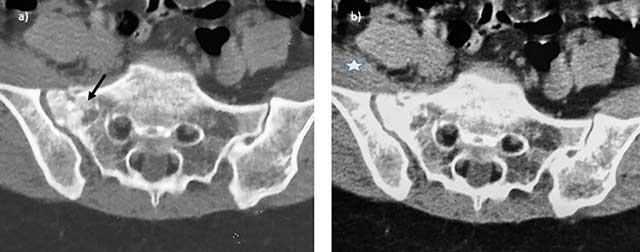

Figure 5

Stress fracture of the sacrum postpartum. Axial CT views in bone a) and soft tissue b) Reconstructions show the fracture line (arrow) of the right sacrum with soft tissue swelling (asterisk).